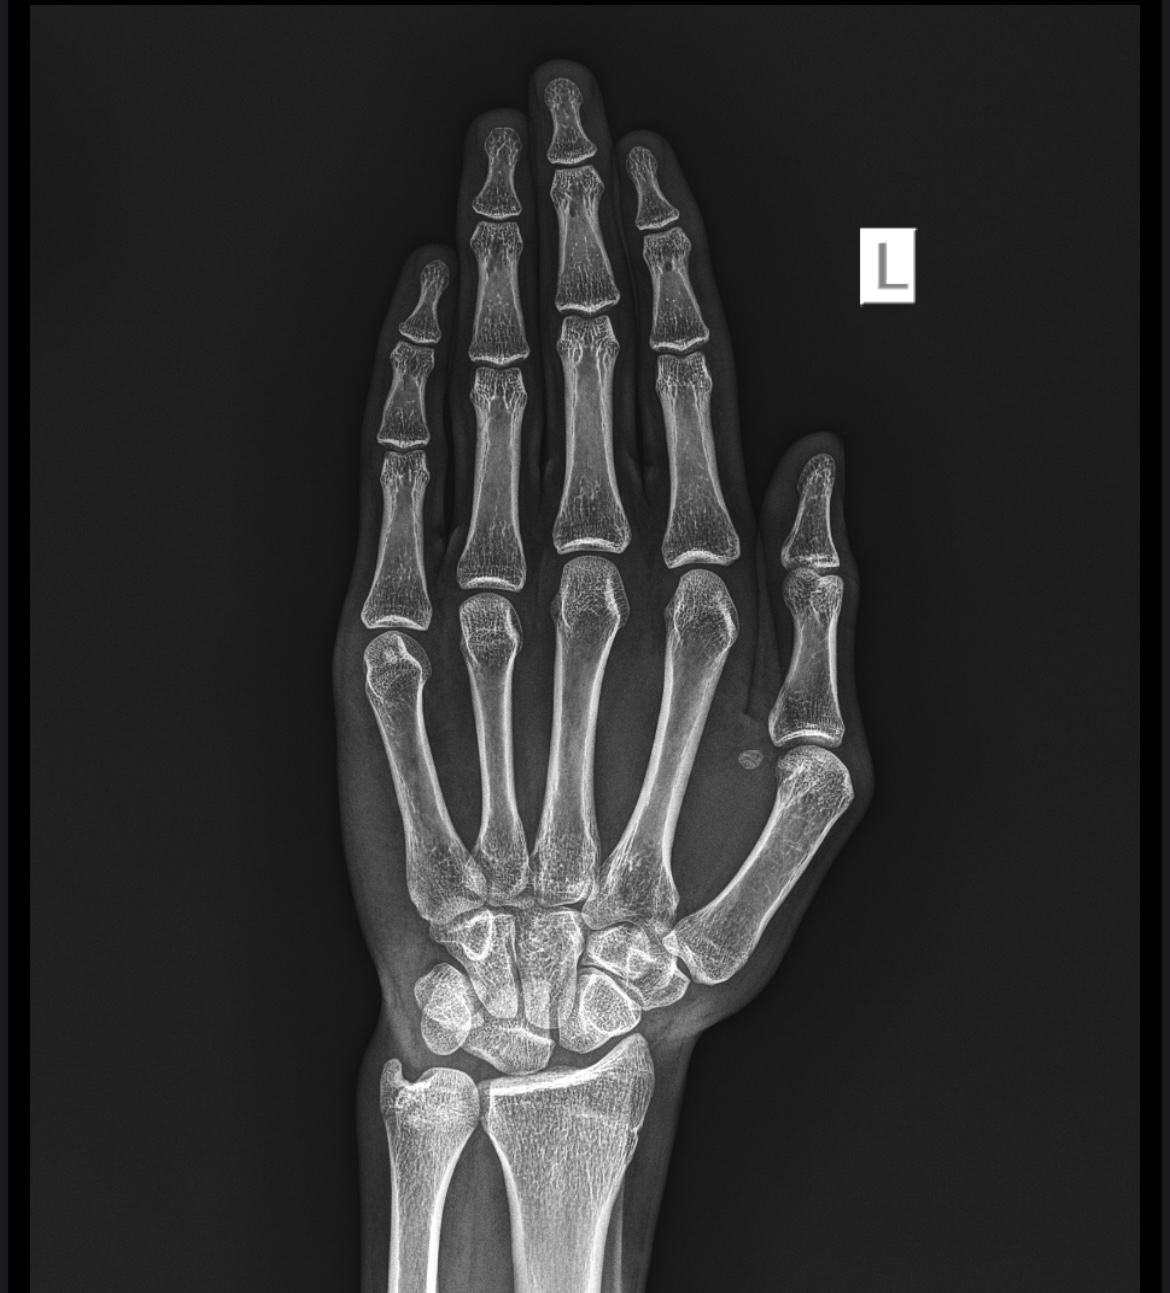

Growth plates open at 18?

IMG 6940

They are almost fused tho, how many cms or mms I can grow?

It looks pretty closed

Na closed rip